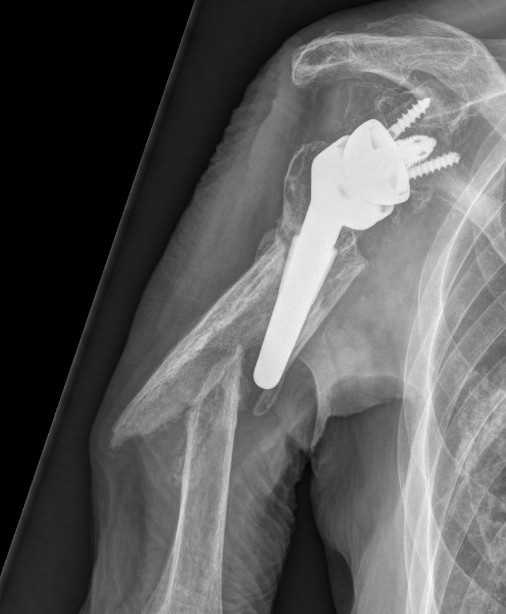

Inferior scapula notching

NotchingGlenosphere overhang

Scapula notching.  Prevented by inferior glenosphere overhand (Depuy Synthes Delta Xtend)

Mechanism

Impingement of humerus component on scapular neck

With arm in extension / adduction / external rotation

Prevention

Glenosphere position

- inferior hang - eccentric glenosphere design

- inferior tilt

- lateralization